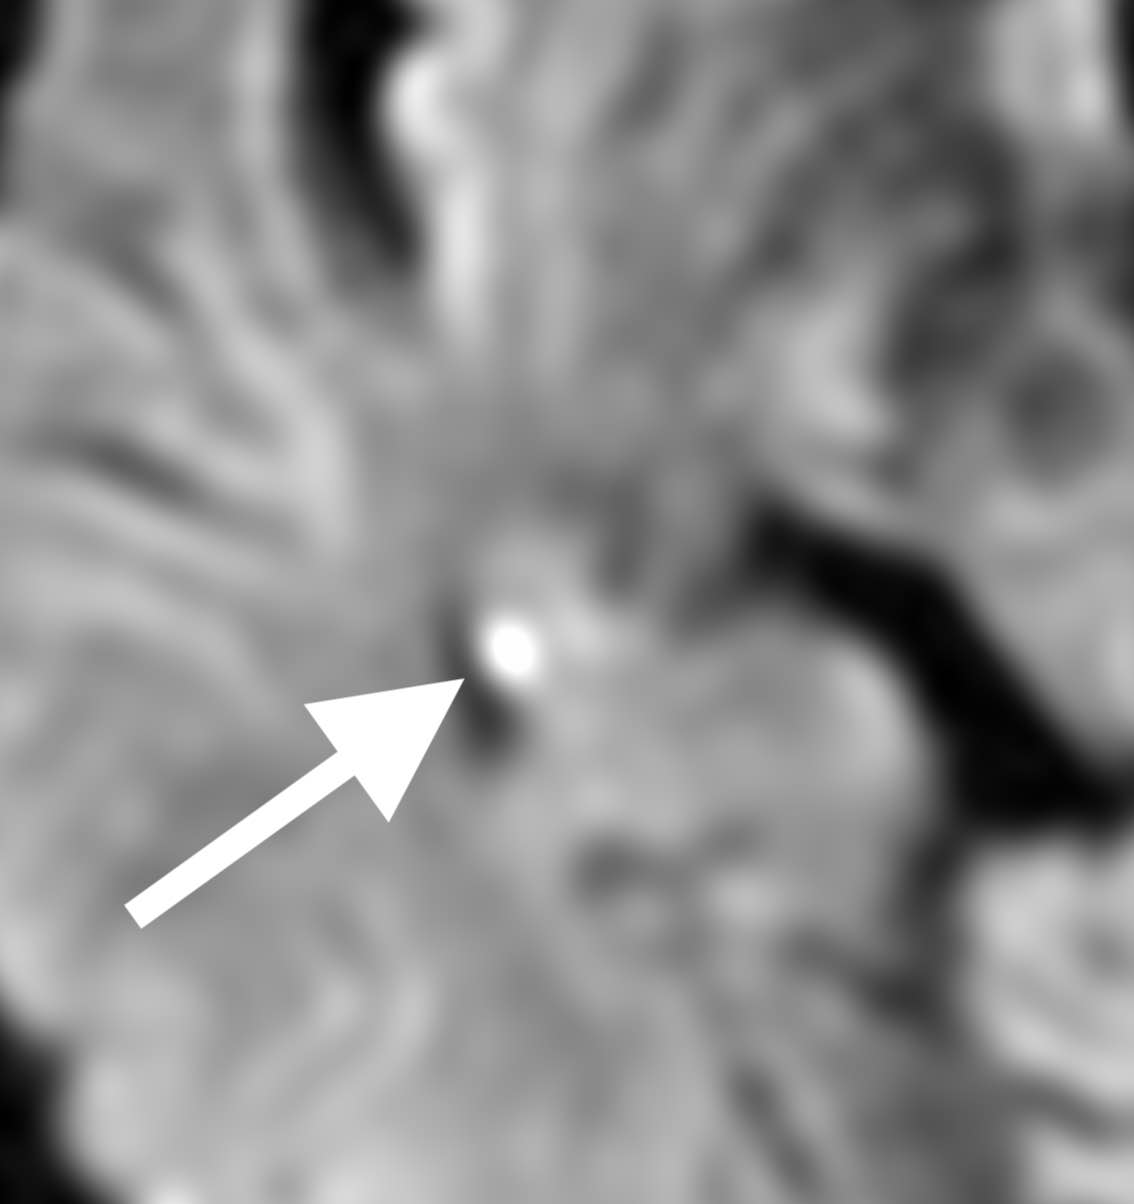

MRI検査(拡散強調画像)で見たところ、

左の海馬(記憶に関係する場所)に白く光っている部分があり、きわめて小さな脳梗塞と考えられました。

このMRI画像所見から、一過性全健忘と診断しました。